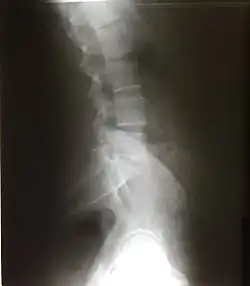

Scalloping vertebrae is the increase in the concavity of the posterior vertebral body. It can be seen on lateral X-ray and sagittal views of CT and MRI scans. Its concavity is due to the increased pressure exerting on the vertebrae due to a mass. Internal spinal mass such as spinal astrocytoma, ependymoma, schwannoma, neurofibroma, and achondroplasia causes vertebrae scalloping.[20]